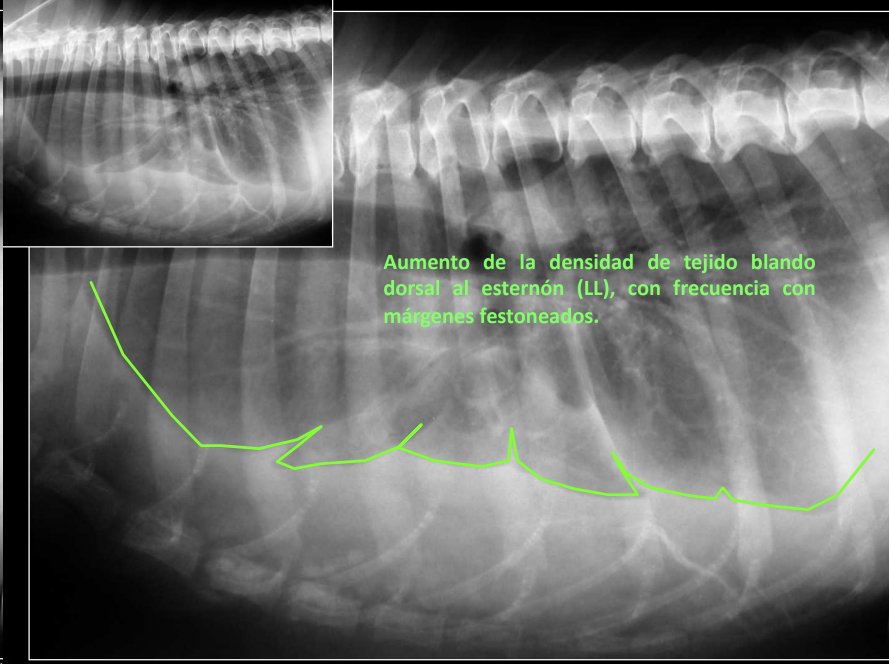

Derrame pleural

- Líquido en espacio pleural (uni/bilateral).

- RX: